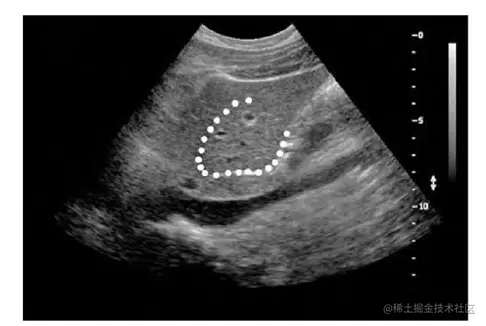

下图(图6)显示了二流腔静脉的超声图像(图的下三分之一处为钝区)。肝脏的分割,被白色斑点包围的区域,显示出与周围组织相比独特的纹理。

图6,利用纹理分析的医学图像